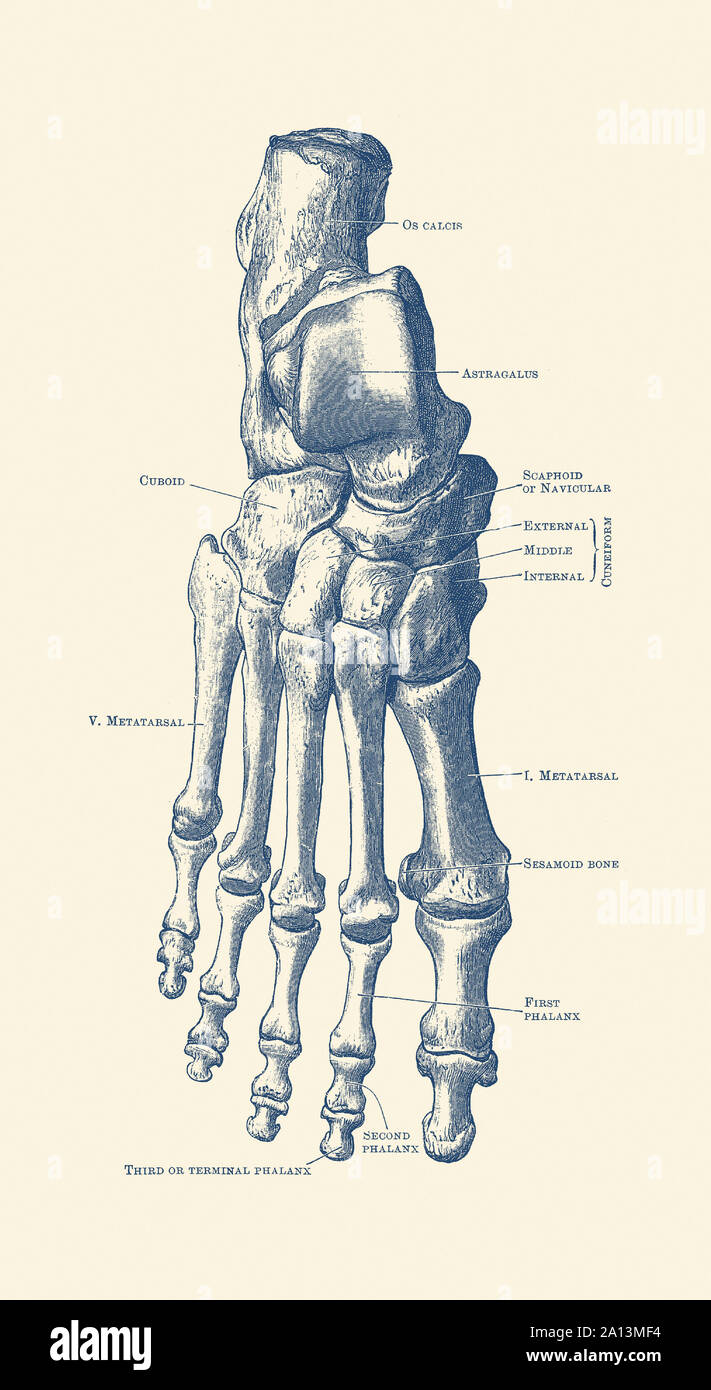

RF2DHMD0H–OS du pied. Anatomie humaine. Le schéma montre l'emplacement et le nom de tous les os du pied.

RM2A83MWT–Opinions de l'os dans le pied humain, de la cheville aux pieds. La gravure sur cuivre par Edward Mitchell après une illustration anatomique par Jean-Joseph Sue de John Barclay's une série de gravures du squelette humain, MacLachlan et Stewart, Édimbourg, 1824.

RMK228DY–Partie terminale du membre inférieur, reposant sur le sol au cours de posture droite ; le squelette du pied a 26 os.

RF2BTGDWM–Les os de la Tarsal du pied sont situés dans le milieu du pied et les zones de l'arrière du pied humain, dessin de ligne vintage ou illustration de gravure.

RMK227XM–Partie terminale du membre inférieur, reposant sur le sol au cours de posture droite ; le squelette du pied a 26 os.